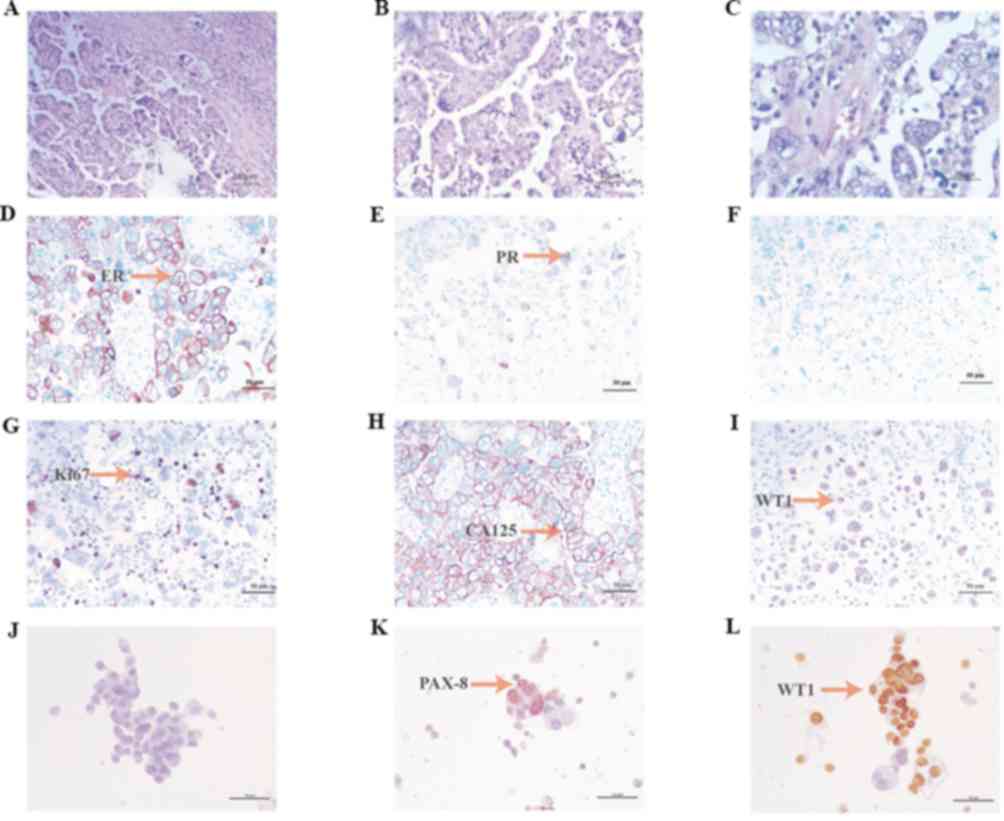

The biopsy sections (thickness, 3–4 µm) were

paraffin embedded, fixed with 4% neutral buffer formaldehyde

solution, at room temperature (25°C) for 6–48 h. Pathological

biopsy was performed at the Fourth Hospital of Hebei Medical

University (Shijiazhuang, China). Hematoxylin and eosin staining of

tumor tissue was performed by optical microscopy (magnification,

×460) and microscopy images were obtained (Fig. 2A-C). Paraffin-embedded slices were

stained with IHC markers (Ventana Benchmark Ultra automatic

immunohistochemical staining platform, primary antibodies: ER:

Anti-estrogen receptor (SP1) rabbit monoclonal primary antibody,

Roche, catalog number: 790–4325; PR: Anti-progesterone receptor

(1E2) rabbit monoclonal primary antibody, Roche, catalog number:

790–4296; P53: Anti-P53 mouse monoclonal primary antibody, Roche,

catalog number: 800–2912; Ki-67: Anti-Ki-67 (30–9) rabbit

monoclonal primary antibody, Roche, catalog number: 790–4286; CEA:

Anti-CEA (COL-1) mouse monoclonal primary antibody, From: MXB

Biotechnologies, catalog number: Kit-0008; CA125: Anti-CA125

(TA347) mouse monoclonal primary antibody, MXB Biotechnologies,

catalog number: MAB-0007; WT1: Anti-WT1 (MX012) mouse monoclonal

primary antibody, MXB Biotechnologies, catalog number: MAB-0678;

PAX-8: Anti-PAX-8 rabbit polyclonal primary antibody, MXB

Biotechnologies, catalog number: RAB-0657; PAX-2: MXB

Biotechnologies, catalog number: RAB-0648. Secondary antibodies:

MaxVision DAB, From: MXB Biotechnologies, catalog number: KIT-5220.

All antibodies were purchased in their ready-to-use format so

dilutions weren't required. IHC experimental procedure according to

the manufacturer's protocols), the percentage of positive staining

was calculated by eye. Immunohistochemistry (IHC) for estrogen

receptors demonstrated a high (70%) expression level in cancer

cells (Fig. 2D). IHC for progesterone

receptors revealed a moderate (30%) expression level in cancer

cells (Fig. 2E). IHC for p53

demonstrated zero expression level of p53 in cancer cells (Fig. 2F). IHC for Ki67 revealed a moderate

(30%) expression level in cancer cells (Fig. 2G). Staining for cancer antigen 125

demonstrated a high expression level (Fig. 2H). IHC for Wilms tumor protein (WT1)

revealed a moderate expression level in cancer cells (Fig. 2I). IHC for paired box gene PAX-2,

PAX-8 and CEA was also performed, revealing zero, positive and

positive expression, respectively (Fig.

2J-L). An MRI scan was performed, which demonstrated

enhancement of the pelvic tumor (Fig.

3A), enhancement of hepatic metastasis (Fig. 3B,C), and thickening of the omentum

majus and tumor tissue (Fig. 3D).